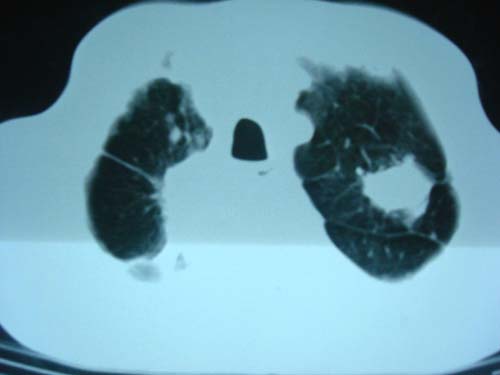

男性,45岁,胸疼,低热,抗炎治疗后症状缓解拍片检查发现左上肺有高密度灶,考虑结核,做ct示条件有限采集了部分图像,图像质量差请谅解

病灶有分叶,毛刺,考虑肺癌可能性大,建议穿刺。

病灶有分叶 毛刺 左侧叶裂上移 考虑肺癌可能性大 建议穿刺

右上肺结核,左上肺周围型肺癌可能性大

考虑两肺上叶继发性肺结核;肺气肿(多发肺大泡)。

团块状病灶,病灶周围长毛刺及灶周肺气肿。